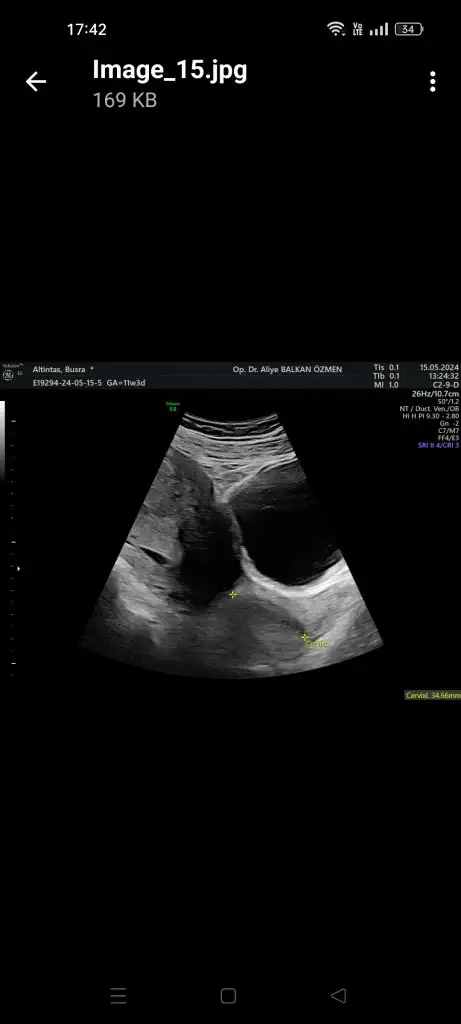

Ya bana da 25 mm üzeri olması gerekiyor dedi benimki 34mm çıktı 15 haftalığız sizin yazınızı görünce içime şüphe düştü şimdi doktorum sorun yok dedi ama ben yine de bayram öncesine randevu alayım bi. Rahim ağzı u şeklindeydi bi ucundan bi ucunu ölçtü demi ?

Bana resmini de verdi dur aticam

Eklentiler

• Screenshot_2024-05-29-17-42-23-66_e307a3f9df9f380ebaf106e1dc980bb6.webp

Screenshot_2024-05-29-17-42-23-66_e307a3f9df9f380ebaf106e1dc980bb6.webp

11,8 KB · Görüntüleme: 46